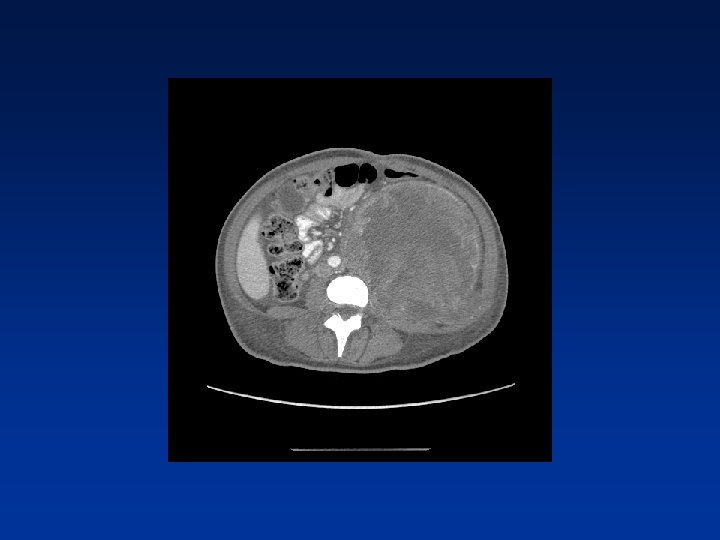

CASE